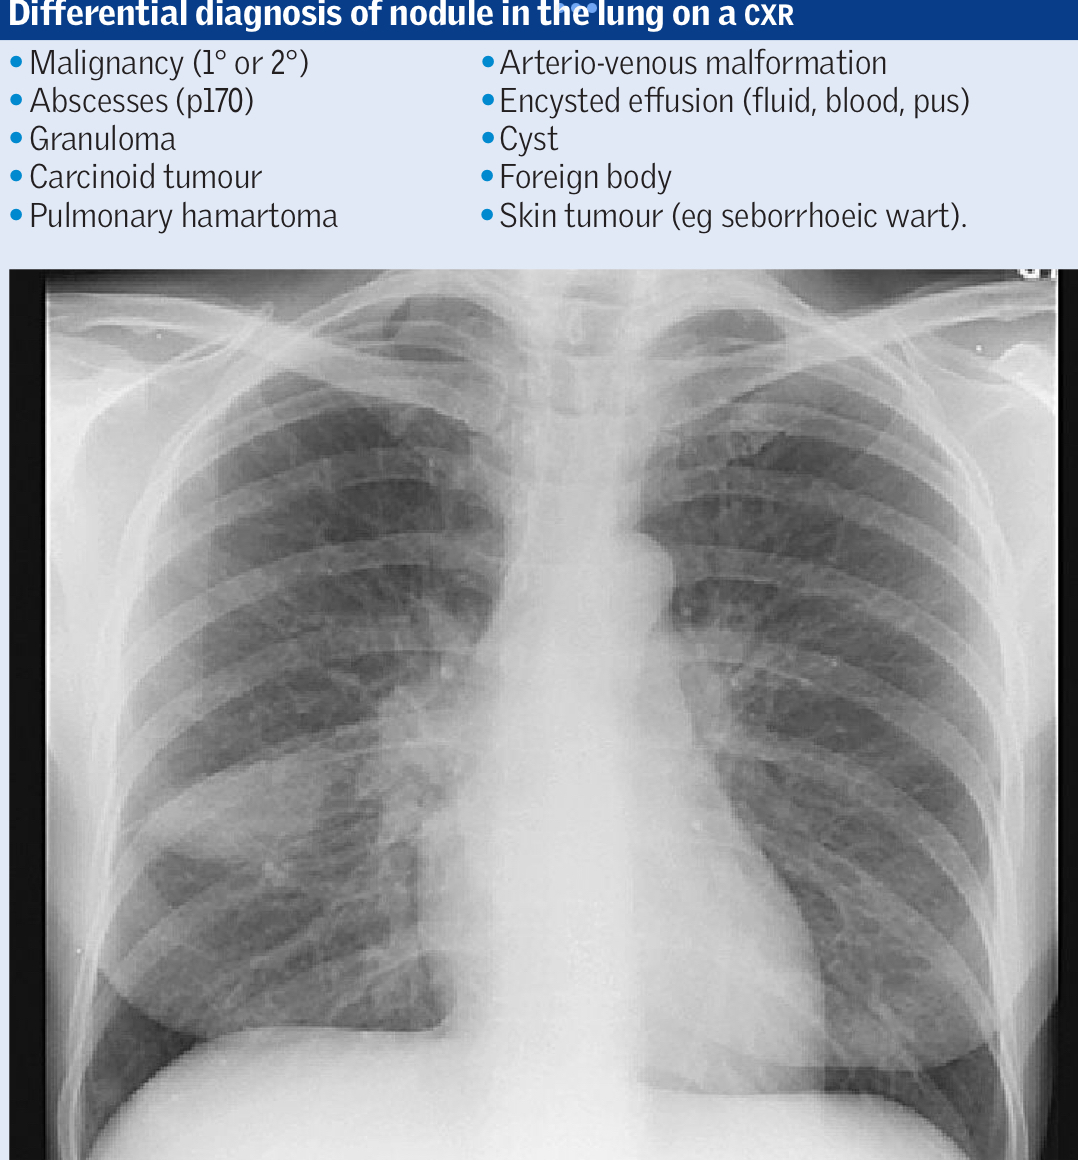

What are some differentials for a pulmonary nodule on CXR other than lung cancer?

A